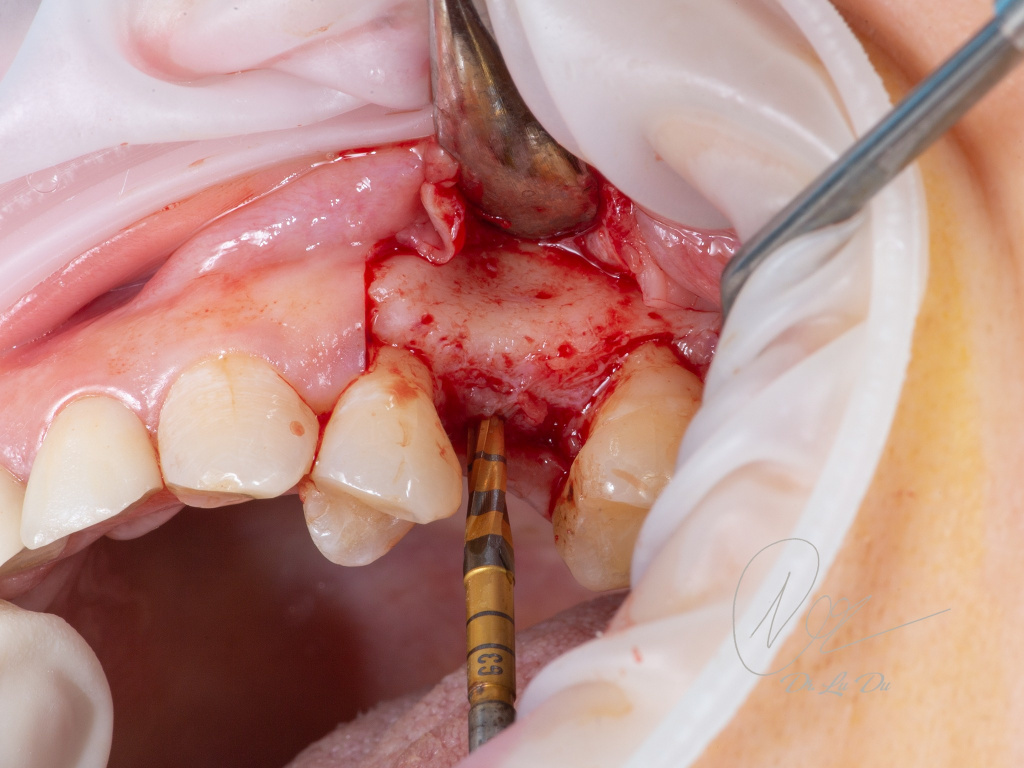

Имплантация AnyRidge с двусторонним закрытым синус-лифтингом.

Осложнения: правосторонний гайморит.

Кейс MINEC: Dr Lu Du